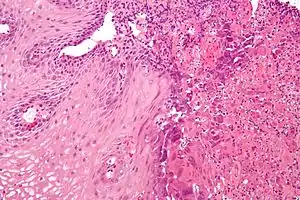

بیماریهای مختلفی مانند دیسفاژی، آشالازی، اسپاسم منتشر مری، بلع دردناک، اسکلروز، ریفلاکس، ازوفاژیت و سرطان میتوانند مری را درگیر سازند.